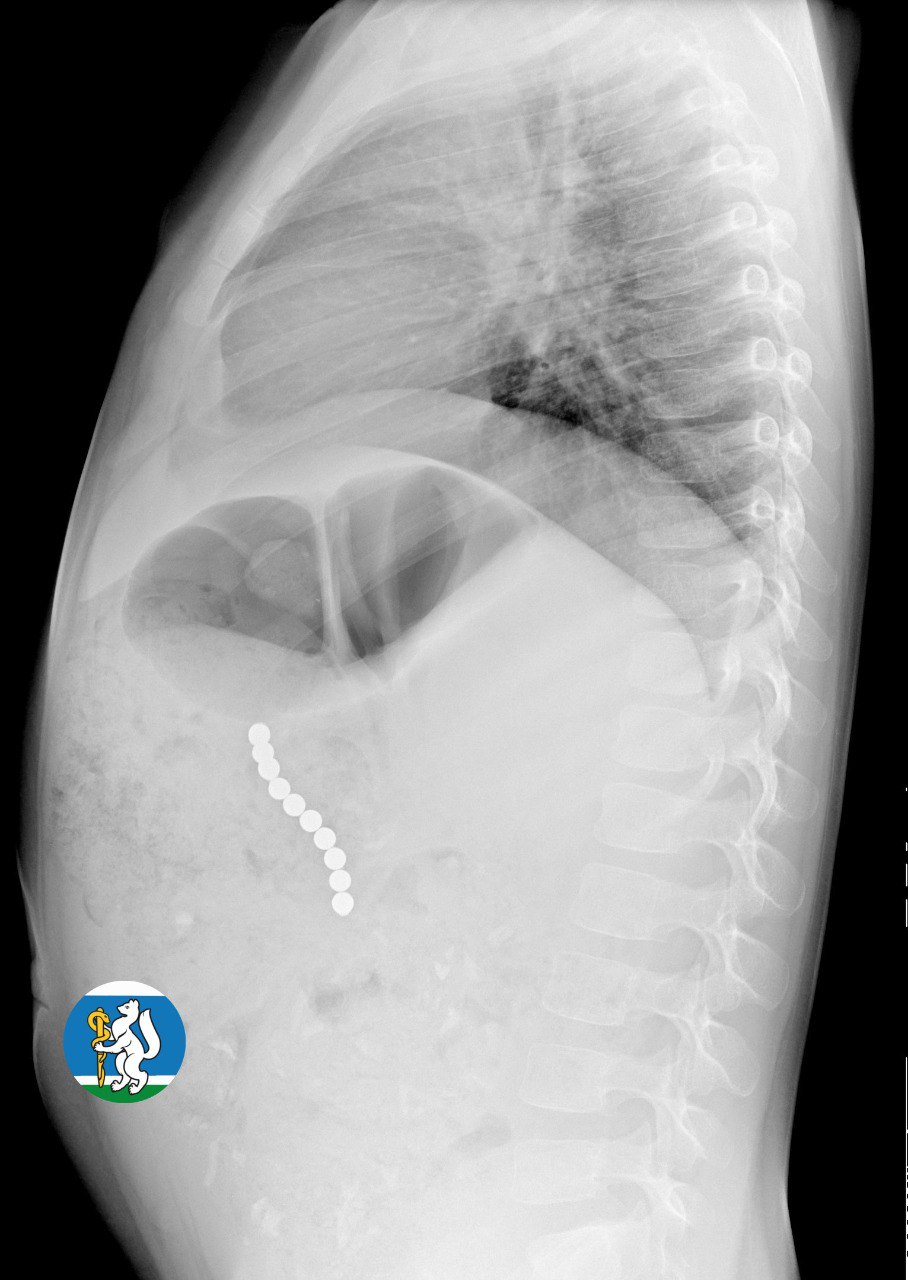

«Малышка почувствовала недомогание, и семья пришла на консультацию к участковому педиатру. Для исключения пневмонии был выполнен рентген органов грудной клетки. Благодаря этому на снимке в проекции желудка диагносты обнаружили чрезвычайно опасный предмет — цепочку магнитных шариков, которые травмировали стенки органов пищеварительной системы и могли стать причиной перитонита. В связи с угрозой жизни Ульяну оперативно госпитализировали в Детскую городскую клиническую больницу №9, где ей оказали всю необходимую помощь», — рассказала глава ведомства.

«Для минимизации риска осложнений удаление инородных тел было проведено интраоперационно. В ходе вмешательства дежурная бригада врачей извлекла 10 магнитных шариков, цепочка которых в длину составила 5 сантиметров», — рассказал детский хирург ДГКБ №9 Андрей Чукреев.